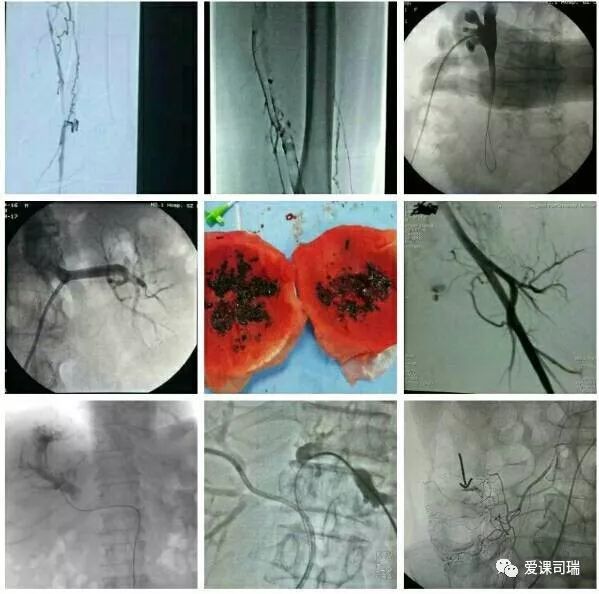

1.有影像设备的引导:在能够“看穿身体”的影像设备帮助下,不需要切开人体,就能看到体内脏器和病变,实现“可视化”。

3.诊断与治疗相融合:介入医生能够通过影像设备直接看到病变,疾病的诊断就很容易明确,随即又可立刻转入治疗过程,实现“诊断治疗一体化”或“诊治一条龙”。整个过程都看得见,治疗过程中又可继续诊断,如果判断效果还没有达到预期,立即追加治疗也非常方便。

总的说来,如果吃药效果不佳,又不能或不愿开刀的病,都可能通过介入方法得到解决。比如动脉、静脉、尿路、胆道等处堵塞,咯血、便血、尿血、呕血,糖尿病下肢冰凉,甚至是顽固性高血压等等,介入医生用针和细小的导管等器材,无须开刀,也许就能顺利解决,见效往往还很快。如果有这些情况,不妨找介入医生看看。

概括地说,介入诊疗有以下优势: 1.可以远道施术:借助于导管等器材,可以从对病人最有利、远离病变的部位入手,将治疗器材送达病变局部,再施行精细的治疗。比如,头部有病,我们可以方便地从大腿跟部进管,经血管插管到头部去,从而避免直接切割或穿刺头部。 2.创伤轻微,容易耐受:借助于影像设备这“第三只眼睛”的引导,无须开刀即能清晰显示病变部位,从而进行准确的治疗操作。 3.可重复性强:由于创伤小,不会造成局部的粘连和组织缺损,因而可以多次反复地进行治疗,直到病变完全康复为止。 4.定位准确:有影像设备作实时的引导和监控,没有视觉盲区,因而可以“指哪打哪”。 5.疗效高、见效快:对很多病变可以起到“立竿见影”的效果。 6.并发症发生率低:也就是说安全性高,由上述多种优势的综合作用所致。 7.方便联合应用多种介入技术:介入诊疗技术种类繁多,各有特色和优势,可以方便地联合应用,取长补短,从而进一步增强治疗效果。

“介入”的应用范围涵盖了头颈、胸腹、四肢等各个部位,涉及神经、心血管、呼吸、消化、泌尿生殖、骨关节等各个系统器官的病变诊治。

介入放射学按诊治目的可分为介入诊断学和介入治疗学,按涉及学科可分为神经介入、心血管介入、肿瘤介入、妇产科介入等学科分支;介入诊疗技术按进入途径则可分为血管性和非血管性两大类介入技术。

在影像设备引导下实施操作是介入诊疗的鲜明特色,故影像设备不可或缺。目前最常用的介入引导设备是DSA机(见下图)。B超、CT、MRI也可引导介入,在定位穿刺、肿瘤消融等方面也各具优势。